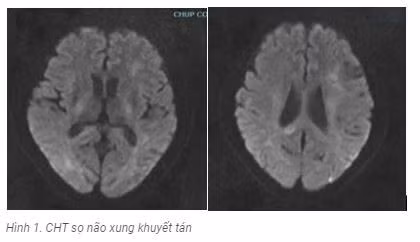

Kết quả CHT sọ : tổn thương tăng tín hiệu trên xung khuyết tán tổn thương chủ yếu vùng vỏ não thùy chẩm, đỉnh 2 bên ( hình 1); trên xung Flair tổn thương tăng tín hiệu vùng cuống não phải, dưới đồi phải, tổn thương chất trắng cạnh não thất 2 bên ( Hình 2).

Kết quả chụp cộng hưởng từ não.